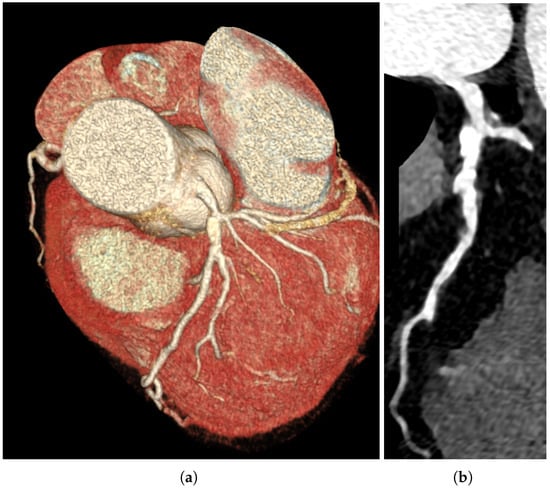

The Great Masquerader: Vasospastic Angina Mimicking Left Main Coronary Artery Disease

A significant proportion of patients undergoing invasive coronary angiography for angina have no obstructive coronary artery disease (CAD). In such patients, coronary microvascular dysfunction (CMD) and vasospastic angina (VSA) represent key pathophysiological mechanisms. We report a case of a 58-year-old male with exertional [...] Read more.

A significant proportion of patients undergoing invasive coronary angiography for angina have no obstructive coronary artery disease (CAD). In such patients, coronary microvascular dysfunction (CMD) and vasospastic angina (VSA) represent key pathophysiological mechanisms. We report a case of a 58-year-old male with exertional chest pain and exercise ECG changes typical of left main or multivessel CAD. Coronary computed tomography angiography (CCTA) showed borderline stenosis of the distal left main coronary artery. Coronary angiography revealed no critical stenosis. A comprehensive functional assessment demonstrated reduced coronary flow reserve (CFR = 2.0) and an elevated index of microcirculatory resistance (IMR = 25), consistent with CMD. An intracoronary acetylcholine provocation test induced severe focal vasospasm of the mid-left anterior descending artery (LAD) with ST-segment elevation and anginal pain, promptly relieved by nitroglycerin, confirming VSA. This case highlights the diagnostic and clinical importance of invasive functional testing in patients with angina and non-obstructive coronary arteries (ANOCA/INOCA). The coexistence of CMD and VSA (two distinct but overlapping pathophysiological endotypes) is increasingly recognized as a marker of adverse prognosis. Functional coronary assessment should be considered in all patients with angina and non-obstructive coronary arteries, as identifying mixed endotypes enables precise, mechanism-guided therapy. Full article